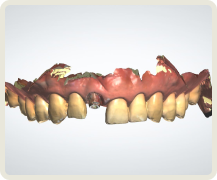

많은 치과의사들이 보철 중심으로 계획된 임플란트 시술의 중요성을 인정합니다.

그리고 이 과정에서 디지털 치과로의 전환이 필요함을 인정합니다.

이제는 임플란트 회사, 임플란트 브랜드 선택의 관점에서 벗어나서 임플란트 수술 진단부터 최종 치아 제작까지. 이 모든 과정에서 보철학적 목표를 디지털 방식으로 어떻게 완성해 내는지가 선택의 관점이 되어야 합니다.

이로운 치과는 간단하고 정확하며 안전한 치료를 위한 디지털 진료 방식을 지향합니다.

잘 못 심은 임플란트의 예시입니다.

이로운 치과는 디지털 진료를 통해 정확한 임플란트 식립 위치를 파악하여

아날로그 치료에서 발생할 수 있는 문제를 예방합니다.

개인 맟춤 디지털 수술 가이드

덴티움 임플란트

환자 맞춤형 지대주

CAD/CAM 지르코니아 크라운

이 모든 술식, 장비, 소프트웨어 노하우가 집약된

이로운치과의 디지털 임플란트